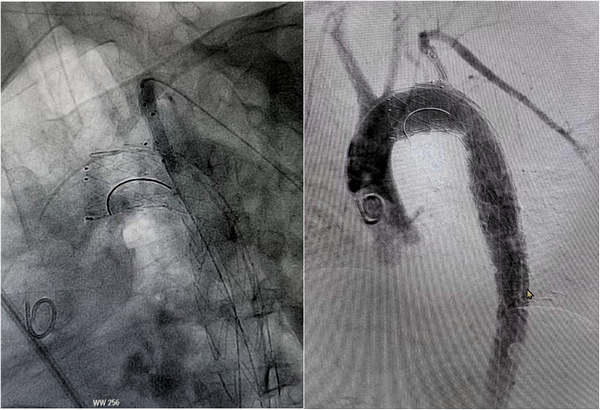

释放支架主体及分支并后扩分支支架:从右侧股动脉引入超硬导丝至升主动脉,沿着超硬导丝送入输送系统并上推至升主动脉,助手配合牵拉分支导丝,使分支支架进入左锁骨下动脉,并使支架窗口对准左侧椎动脉开口,经造影确认支架定位准确后,快速释放主体支架,助手配合牵拉导丝释放分支支架。撤出支架主体,由左侧股动脉导入8-80球囊扩张支架支架,沿左侧股动脉入金标导管至升主动脉,造影显示支架有效封堵夹层破口,无移位和内漏现象发生,左椎动脉与左锁骨下动脉血流通畅,手术圆满成功。